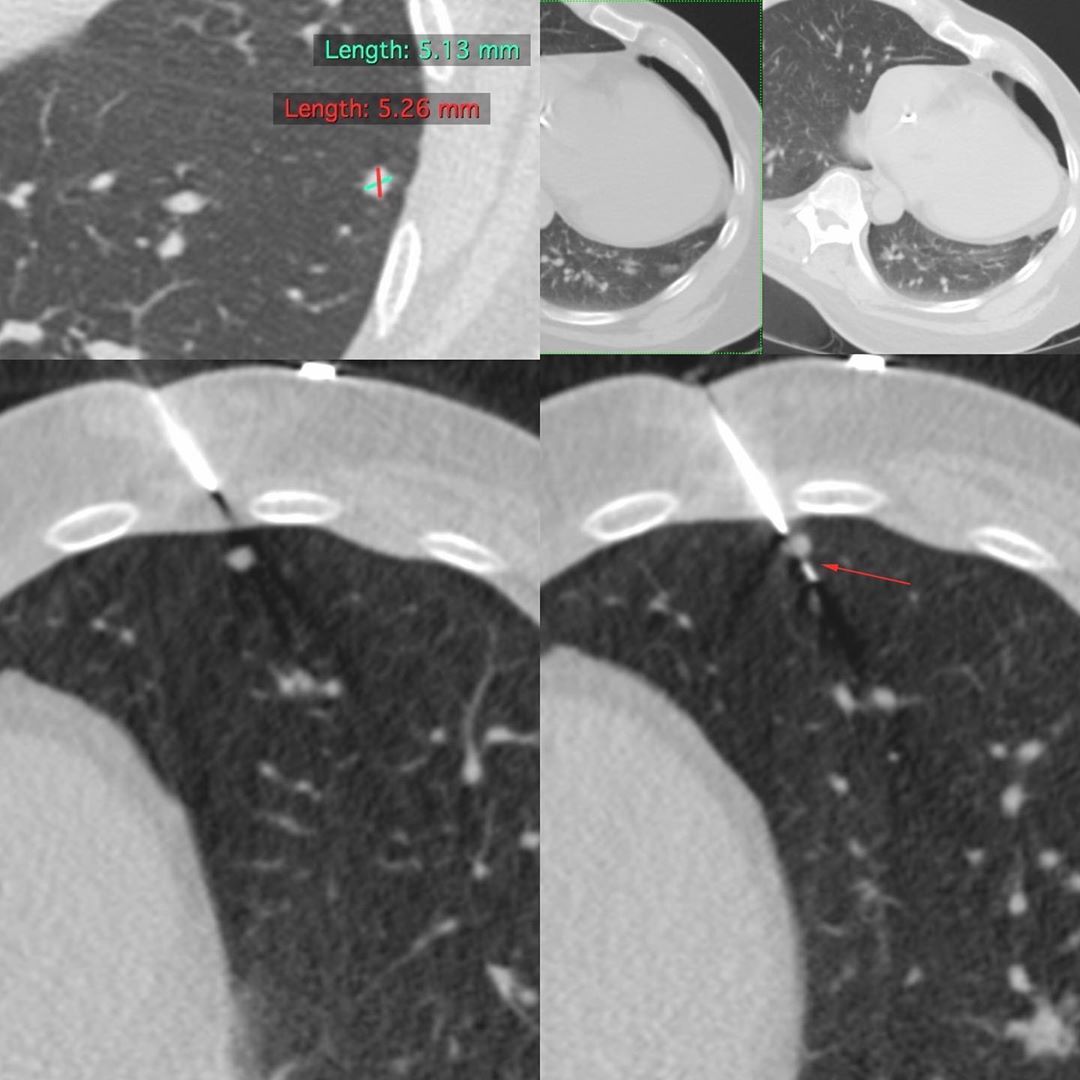

The CT scan showed that the largest, most accessible nodule measured 5.13 x 5.26 mm.

The patient’s free-breathing was shallow and under control. In the right lateral decubitus position, it was possible to biopsy the nodule successfully using a 20G coaxial biopsy gun with a 10 mm throw. There was a 20 cc pneumothorax that remained stable after 1 hour.